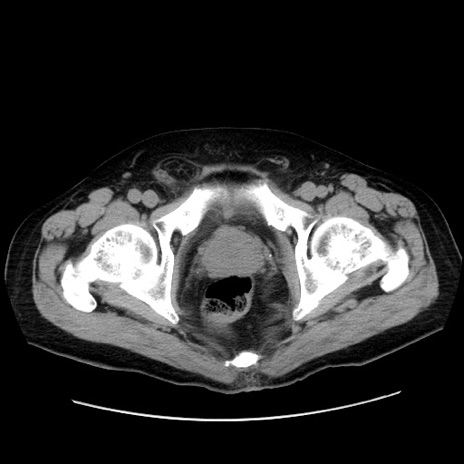

症例30(横断像)

【症例】80歳代男性

【主訴】臍周囲痛

【現病歴】約6時間前から臍下部痛が出現。次第に腹部膨隆・背部痛も生じてきたため来院。背部痛の場所は変化しない。

【既往歴】腎盂腎炎

【身体所見】意識清明、BT 36.3℃、BP  131/87mmHg、P 87bpm、SpO2 100%(RA)、臍周囲自発痛・圧痛あり、反跳痛なし、自発痛部位に一致して板状硬あり、腹部膨隆、腸雑音減弱、CVA tenderness両側陰性。

【データ】WBC 19600、CRP 0.33